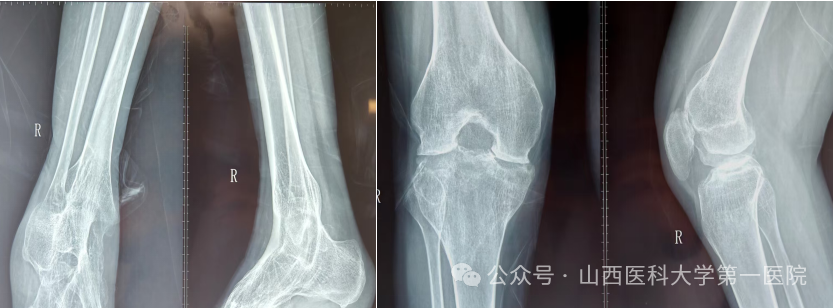

一名42岁的强直性脊柱炎患者,多年来饱受病痛折磨。随着病情进展,双侧髋关节逐渐“锈死”,无法弯腰、下蹲,甚至连坐下都成了奢望——吃饭只能站着,休息只能躺着,生活自理能力几乎丧失。接诊后,骨科杨自权主任团队对患者进行全面检查,发现患者不仅脊柱强直呈“板状腰”,双侧髋关节出现严重融合,而且双膝、双踝关节功能明显下降,手术难度极大。

图片